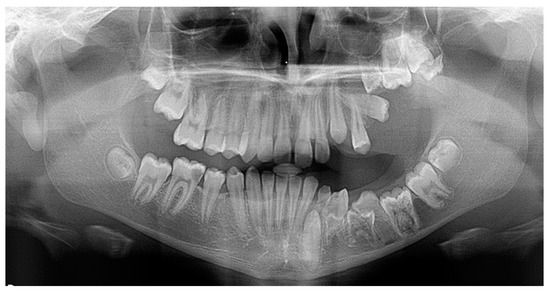

As far as the etiology of impaction is concerned, 205 patients presented one factor responsible for impaction, while 7 presented two. Table 2 shows the ectopic eruption path as the most frequent factor that was reported in 5.29% of total patients examined and mostly reported in maxillary canines. The next most common etiology was the loss of space in the arch (2.50%), followed by the ankylosis of deciduous teeth (1.71%). Concerning the rest of the causative factors, supernumerary teeth other than deciduous were observed in 1.29% of the patients, while the mesiodens was the most frequent supernumerary permanent tooth. In total, 1.21% of the sample presented tumors such as odontoma and osteoma, more often in association with maxillary central incisors. Supernumerary deciduous teeth affected 0.86% of the patients examined, while the ankylosis of permanent teeth was presented in 0.79 of the cases. The maxillary second premolars were the most frequently impacted teeth due to ankylosis. The least common etiology of impaction proved to be the primary failure of eruption, with 3 reported cases out of 212 patients, that following the radiographic examination were all confirmed by genetic tests. Panoramic radiographs indicated for some local etiological factors are presented below (Figure 1, Figure 2, Figure 3 and Figure 4).

Regarding odontoma, it has been stated that the anterior maxilla is the most common site for its development [30], in accordance with the results of our study, where maxillary central incisors were most frequently involved. Isola and colleagues (2017) [11], during their study among 45 patients with odontomas, reported maxillary central incisors and canines as the most affected teeth.

Figure 4. Odontoma in the anterior maxilla.